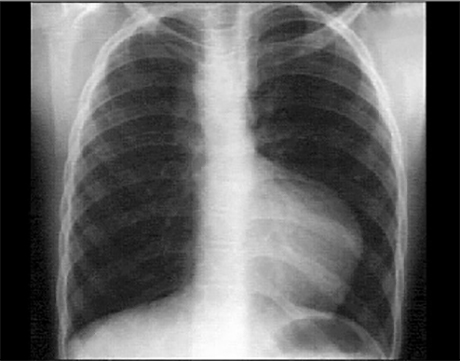

These chest X ray shows right ventricular enlargement, a small pulmonary trunk and decreased pulmonary vascularity. The PA view suggests right ventricular enlargement, as evidenced by the upturned apex. The small pulmonary trunk is evidenced by the absent convex shadow in the left hilar area. Pulmonary vascularity is also diminished, as evidenced by the absence of distal vascular lung markings. These findings are characteristic of tetralogy of Fallot. Note also the right-sided aortic arch demonstrated by the vascular density along the upper right heart border and the displacement of the trachea to the left. Right-sided aortic arch is seen in about twenty-five percent of patients with tetralogy of Fallot.